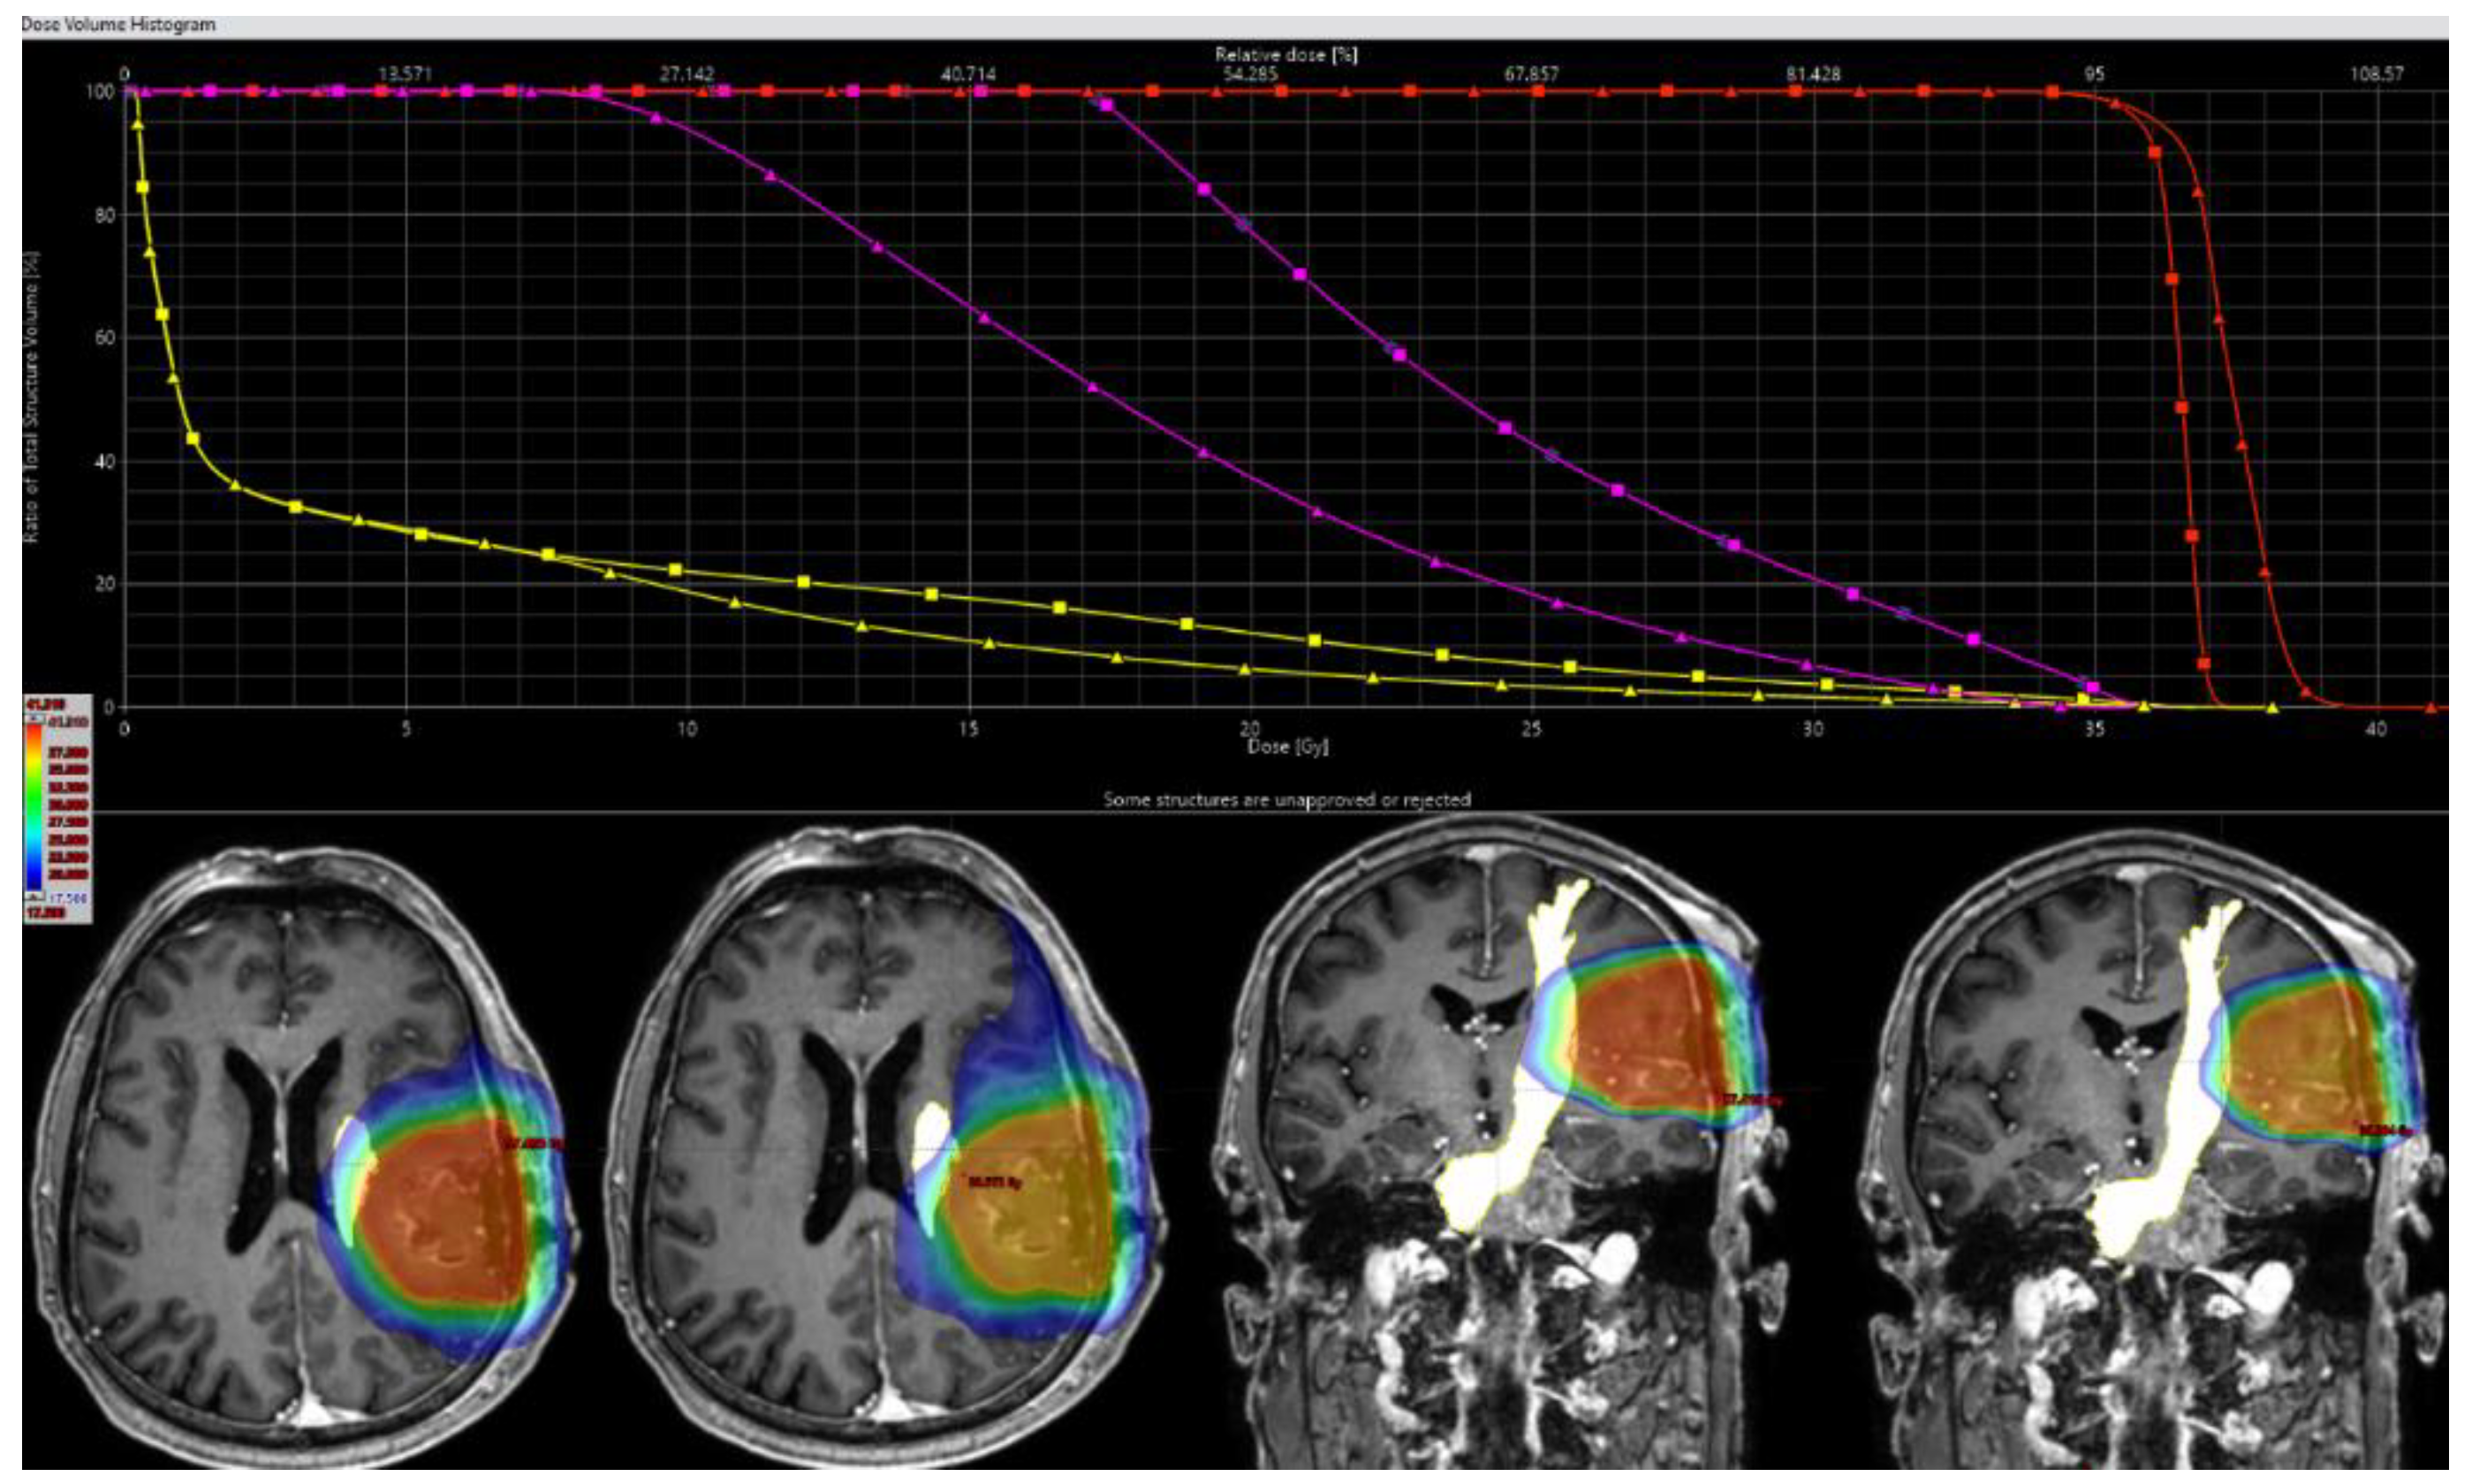

Figure 3.

This figure illustrates the external beam plans for radiation therapy (RT) planning in one patient with a metastasis affecting the parietal lobe. The nTMS based DT-FT are seen delineated as organ at risk (FTmot.tms) in yellow and PTV in red. Of note, there is a slight overlap of the PTV with FTmot.tms. Dose distribution is portrayed in dose color wash from high (red) to lower (green to blue) dose. Each of the left planar views show regular treatment planning without taking FTmot into account. On both the left axial and coronal slide dose distribution is shown for regular plans, each of the right planes depicts dose for optimized plans. The higher dose is drawn away from the fiber tract. On a dose-volume histogram (DVH), dose reduction is seen as a steeper gradient for FTmot.tms outside the PTV (FTmotexPTV) after optimization (yellow line, triangle), compared to the original RT treatment plan (yellow line, quadrate). Accordingly, the FTmot.tms areas beyond the PTV and within the 50% isodose line (FTmotexPTV50%) are displayed in magenta. DVH for PTV is equal up to a relative dose of 95%, but with a higher maximum dose (red lines).